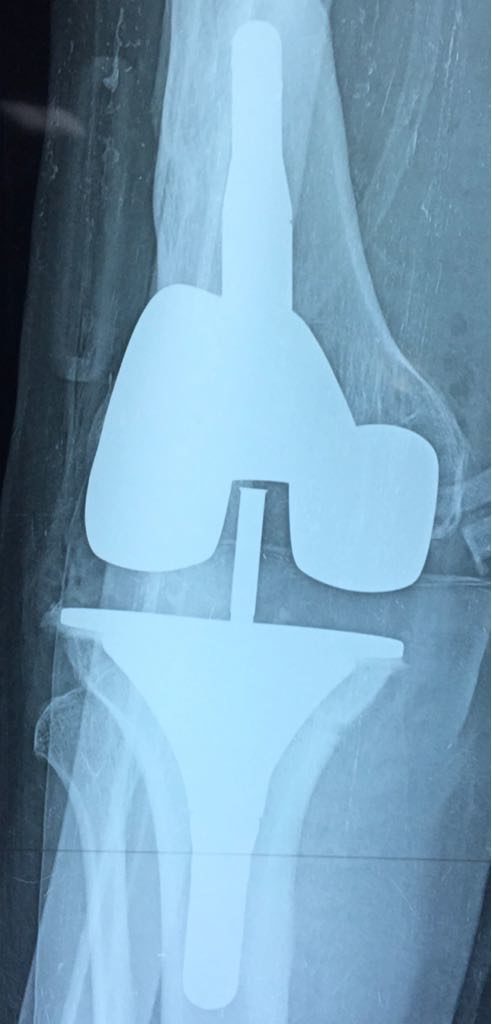

Radio post-Operatoire de PTG de reprise pour une meilleure stabilité du genou